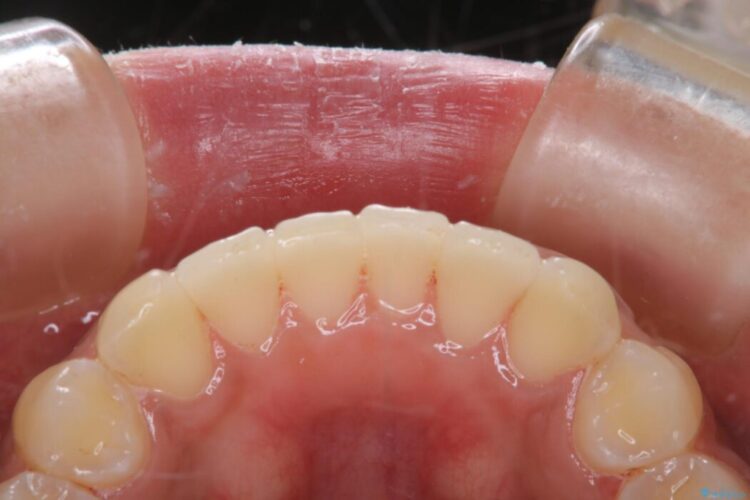

ステインがこびりついていたため、PMTC60分コースを行いました。

PMTCでは、専門の機材を使用し、歯の表面の凸凹にミネラルを補給して、ツルツルの表面に仕上げます。定期的にPMTCを行うことにより、歯質の強化になり着色がつきにくい状態になります。